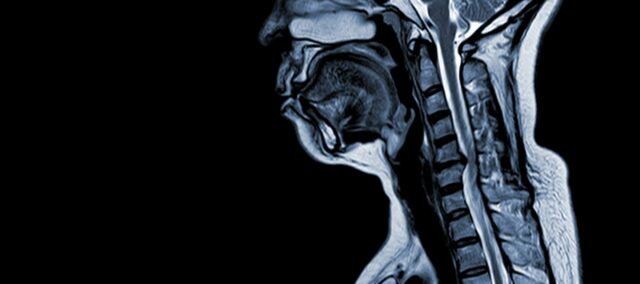

Cervikální spondilotická myelopatie (CSM) je neurologický stav, který je hlavní příčinou poranění míchy u dospělých. Jednoduše řečeno, jedná se o kompresi nebo poškození míchy v krku, především v důsledku přirozeného procesu stárnutí, který postihuje krční obratle. Termín „myelopatie“ pochází z řeckých slov „myelon“, což znamená „mícha“ a „patos“, což znamená „nemoc“.

CSM je komplexní zdravotní stav s multifaktoriální patofyziologií, která zahrnuje strukturální změny v krční páteři. K jeho rozvoji a rozvoji přispívá několik klíčových faktorů:

- Degenerace disku (vyboulení disku) : CSM často začíná degenerací meziobratlových plotének v krční páteři, což způsobuje jejich vyboulení nebo vyčnívání do páteřního kanálu.

- Subperiostální kostní formace (ventrálně od páteřního kanálu): V reakci na zvýšené mechanické namáhání vytváří tělo novou kostní tkáň na přední (ventrální) straně páteřního kanálu, čímž se může zúžit prostor pro míchu.

- Osifikace zadního podélného vazu: Zadní podélný vaz může podléhat osifikaci, tvrdnutí a kalcifikaci, což přispívá k zúžení páteřního kanálu.

- Hypertrofie ligamentum flavum: Hypertrofie ligamentum flavum způsobuje jeho zesílení a snížení pružnosti, což dále zasahuje do prostoru páteřního kanálu a stlačuje míchu.

Tyto strukturální změny společně vedou k útlaku a zúžení páteřního kanálu, což má za následek charakteristické příznaky a komplikace spojené s CSM. Rozpoznání těchto rizikových faktorů a pochopení patofyziologických mechanismů je zásadní pro prevenci i léčbu. Pro zmírnění dopadů těchto strukturálních změn na míchu je zásadní včasná diagnóza a vhodná intervence.